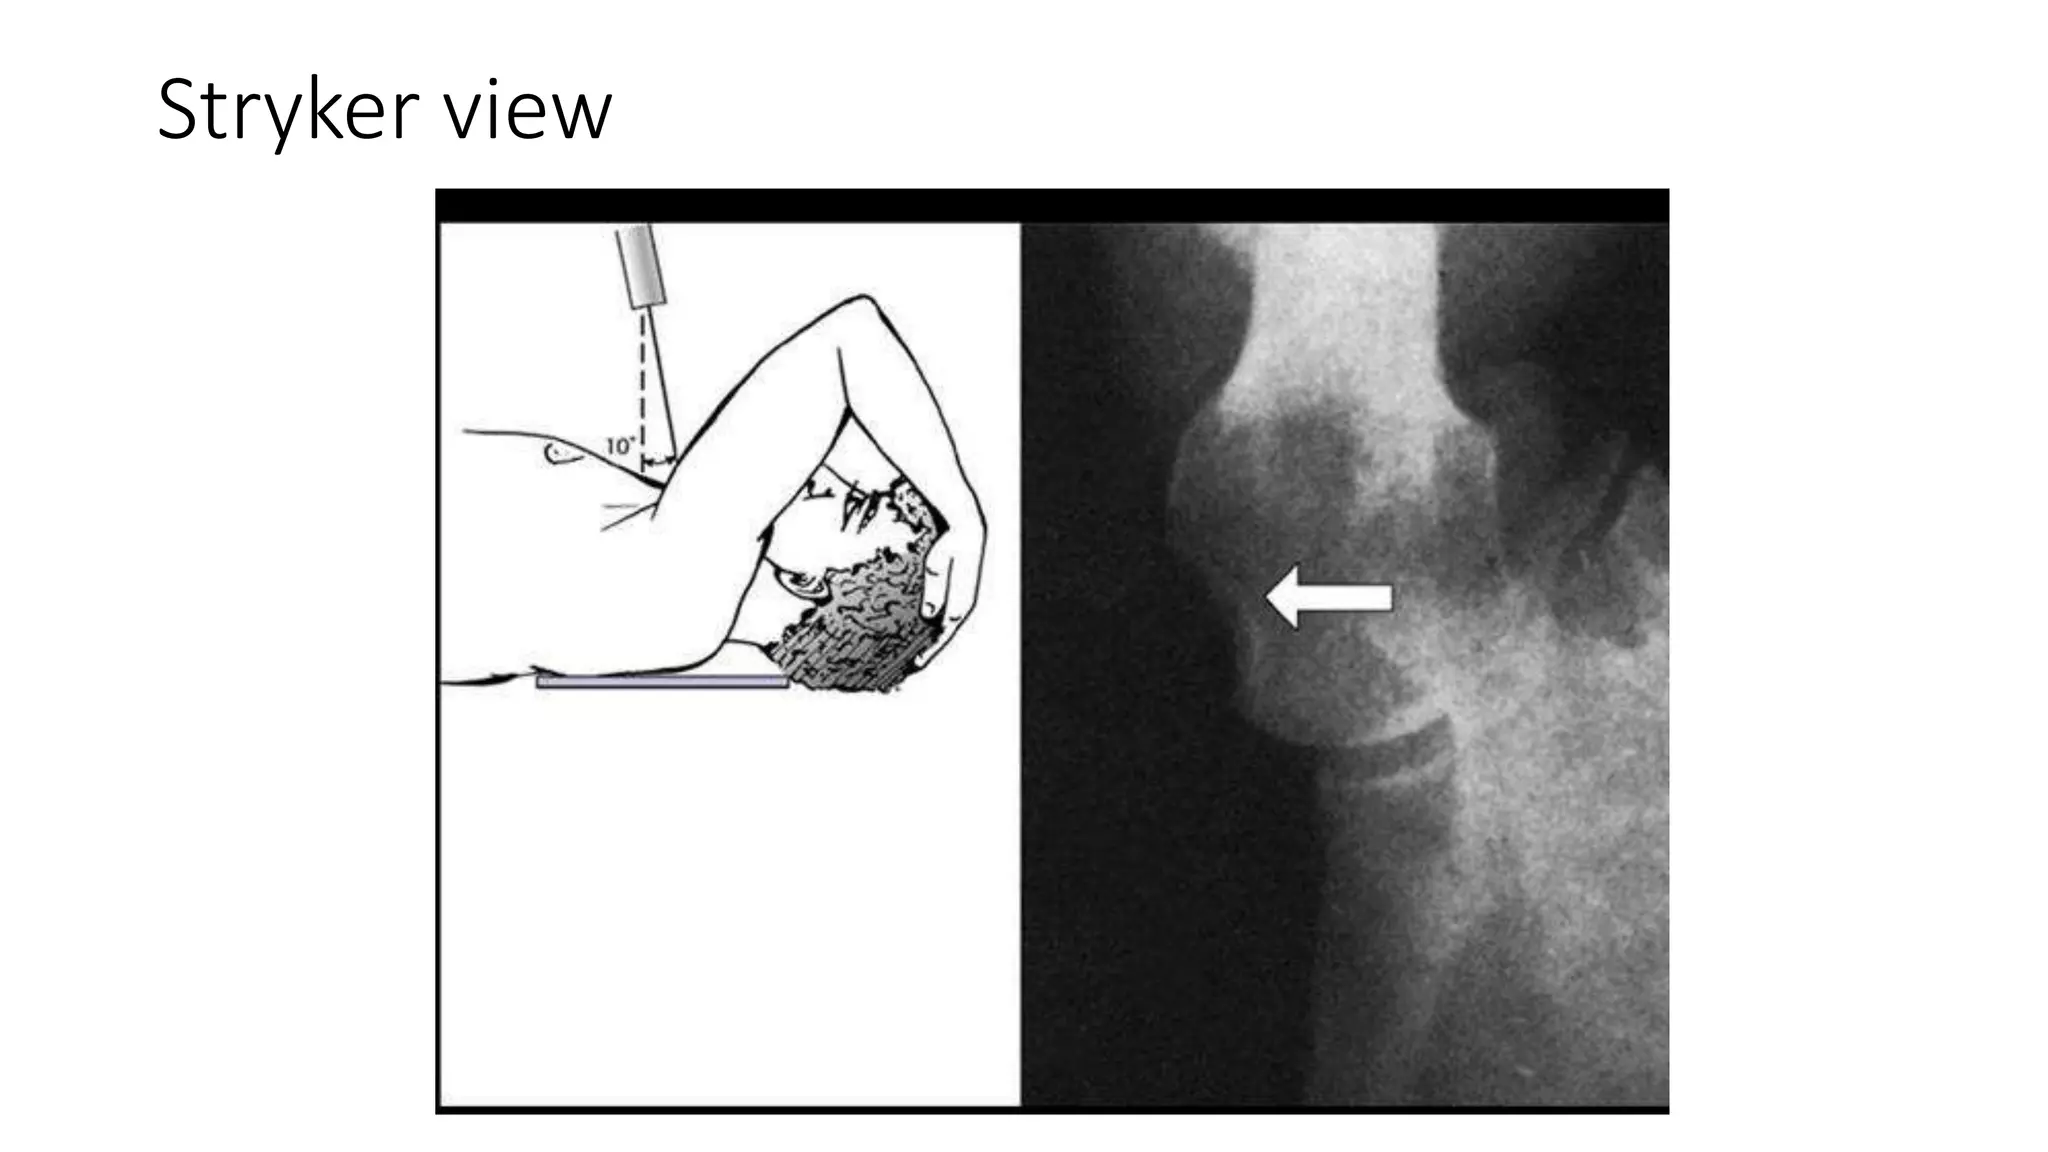

• Stryker view :- shows Hill-Sachs lesion

Stryker view

Imaging Radiographs • true AP •scapular Y • axillary other helpful views • West Point view :- shows glenoid bone loss • Stryker view :- shows Hill-Sachs lesion • CT scan • helpful for evaluation of bony injuries • MRI • best for visualization of labral tear • addition of intraarticular contrast • increases sensitivity and specificity